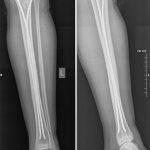

Այս ուսումնասիրությունը հիմնված է 21 հիվանդների (17 տղա, 4 աղջիկ) շարունակական խմբի բուժման արդյունքների վերլուծության վրա, որոնք ենթարկվել են տիտանե էլաստիկ մեխերով վիրահատության։ Հիվանդների տարիքը եղել է 4 տարեկանից մինչև 16 տարեկան։ 9 երեխայի մոտ կոտրվածքի պատճառ է հանդիսացել ձեռքի վրա անկումը, մնացածի մոտ կոտրվածքն առաջացել է վերջույթի ոլորման արդյունքում, վնասվածքի մեխանիզմը եղել է ուղիղ: 19 դեպքերում կոտրվածքները եղել են փակ, իսկ 2 դեպքում՝ բաց։ Ըստ վնասվածքի տեղայնացման՝ դրանք եղել են դիաֆիզար կոտրվածքներ (15 դեպք), պրոքսիմալ մետաֆիզի մակարդակի կոտրվածք (3 դեպք) և հեռավոր մետաֆիզի՝ (3 դեպք): Կոտրվածքային գծի բնույթի համաձայն՝ դիաֆիզային կոտրվածքներից հայտնաբերվել են 6 լայնակի, 4 թեք, 5 պտուտակաձև։ Մի տղայի մոտ (4 տարեկան), որի մոտ առկա էր սրունքի մ/3-ի բաց թեք կոտրվածք տեղաշարժով և մաշկի մինուս հյուսվածքներով, կատարվել է նաև վերքերի առաջնային վիրաբուժական մշակում և կարում՝ ռետինյա արտաթորիչներով։ Սակայն մի քանի շաբաթ անց սկսվել է մաշկի նեկրոզ։ Այդ իսկ կապակցությամբ կատարվել է երկրորդ վիրահատական միջամտությունը։ Կատարվել է մաշկի աուտոտրանսպլանտացիա։ Մաշկի կտորները վերցվել են առողջ ազդրի առաջային մակերեսից: (Նկ 1)